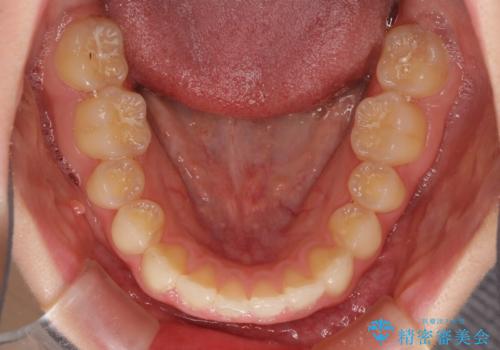

上顎のみの抜歯矯正 前歯のデコボコを改善する

- 上顎前歯のデコボコを気にして来院された患者様です。

口元の突出感はなく、上顎のみに顕著な叢生が認められました。

上顎の左右第一小臼歯2本を抜歯し、ワイヤー装置にて歯列を整えることとしました。

奥歯の咬み合わせがなかなか定まらず、スペースが閉じるまでに時間がかかりましたが、最終的には正中を合わせることもできました。